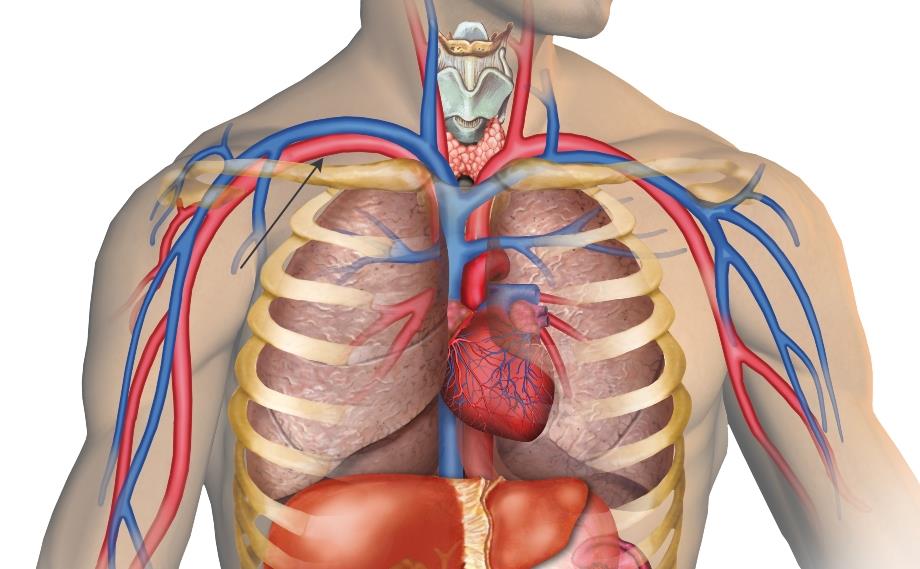

Анатомия Сердца: Расположение и Функции